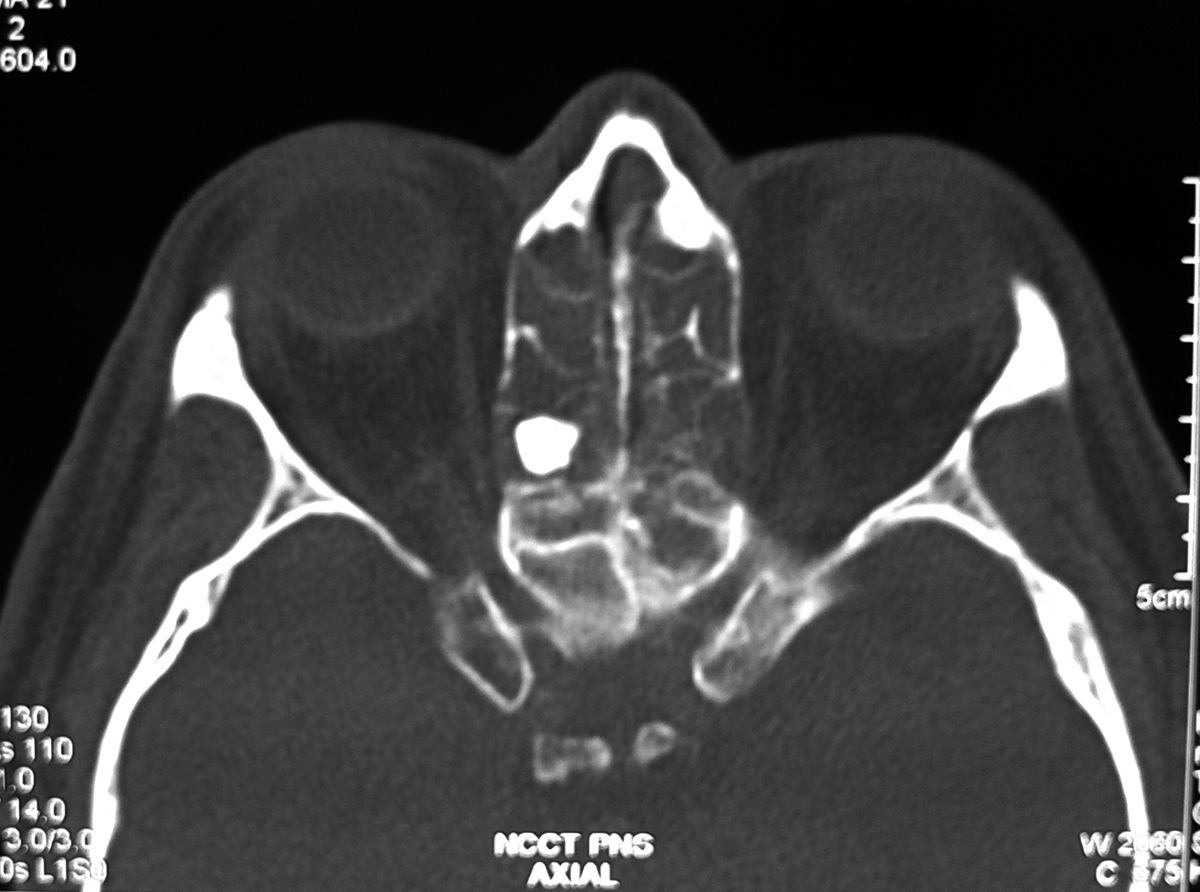

Axial view of the CT scan of the paranasal sinus showing the osteoma of... Download Scientific Maxillary Sinus Osteoma Radiology — for small, asymptomatic osteomas, especially if restrained within the margins of the paranasal sinuses, regular. osteomas are often discovered incidentally during radiologic imaging of the head or sinuses for other reasons, since osteomas frequently do not cause. Symptomatic osteomas require surgical intervention. — maxillary sinus osteomas are benign osteogenic lesions. main treatment option for sphenoid. Maxillary Sinus Osteoma Radiology.